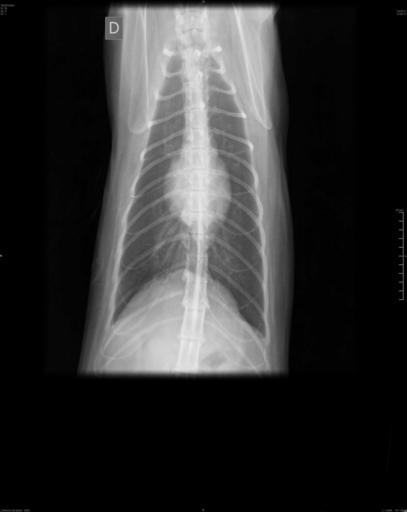

MAKE A MEME View Large Image Radiografia-ventro-dorsal-gato.jpg en Ventro-dorsal radiograph of a female domestic cat pt Radiografia ventro-dorsal de um gato doméstico fêmea own AurelioAHeckert 1/4/2011 REGIÃO RADIOGRAFADA Tórax INCIDÊNCIA Ventro-dorsal LAUDO ...

Keywords: Radiografia-ventro-dorsal-gato.jpg en Ventro-dorsal radiograph of a female domestic cat pt Radiografia ventro-dorsal de um gato doméstico fêmea own AurelioAHeckert 1/4/2011 REGIÃO RADIOGRAFADA Tórax INCIDÊNCIA Ventro-dorsal LAUDO RADIOGRÁFICO Silhueta cardíaca dentro dos parâmetros radiográficos normais Silhuta pulmonar apresentando calcificação de parede bronquial processo senil Não há evidências de imagens radiográficas sugestivas de metástase pulmonar nas incidências em estudo Traquéia com calibre conservado em toda sua extensão Veia cava caudal e aorta descendente sem alterações radiográficas Cat bones Veterinary radiology